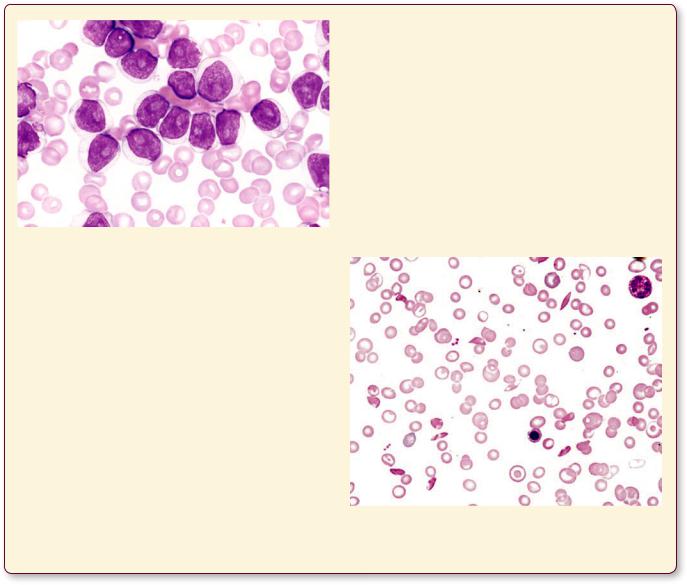

B-Cell Prolymphocytic Leukemia

B-cell prolymphocytic leukemia is a relatively rare form of leukemia that arises relatively late in life, around 60 years of age, and affects males more frequently than females. The histopathologic picture presents bone marrow smears and blood smears with medium to large prolymphocytes. Usually, the disease is accompanied by an enlargement of the spleen. The prognosis is not good because this type of leukemia is quite aggressive and treatment modalities are not very effective; in fact, they are mostly palliative, and usually the patient succumbs in two or three years.

This blood smear, from a patient suffering from B-cell prolymphocytic leukemia, displays numerous large prolymphocytes whose nucleus presents a coarse chromatin network and large vesicles. (Reprinted with permission from Mills SE, Carter D, Greenson JK, Reuter VE, Stoler MH eds. Sternberger’s Diagnostic Surgical Pathology, 5th ed.., 2010. P. 644.)

Sickle Cell Anemia

Sickle cell anemia, a hereditary disease, is the result of a point mutation in the gene that codes for hemoglobin. A single amino acid substitution of alanine replacing glutamine occurs in some individuals who are descendants of the indigenous population of tropical and subtropical regions of Africa, especially from the sub-Saharan area. Approximately 2 per 1,000 African Americans are afflicted with this disease, and 10% of that population carry one copy of the gene and, therefore, are carriers of the trait but are not afflicted by the disease. The red blood cells of patients with two copies of the gene are

defective and carry a reduced amount of oxygen. These erythrocytes are fragile, do not pass easily through small capillaries, and assume a sickle shape. The abnormally shaped red blood cells have a deleterious effect on the kidneys, brain, bones, and spleen among other organs. Depending on the severity of the condition, the patient’s symptoms may vary from slight to severe, and in the latter case, it may result in death at an early age. Since sickle cell anemia is incurable, it is treated with avoidance of strenuous physical exertions, avoiding high altitudes, and instructing patients to seek treatment for even minor infections.

This blood smear, from a patient suffering from sickle cell anemia, displays numerous red blood cells that are distorted so that they appear spindle-shaped.